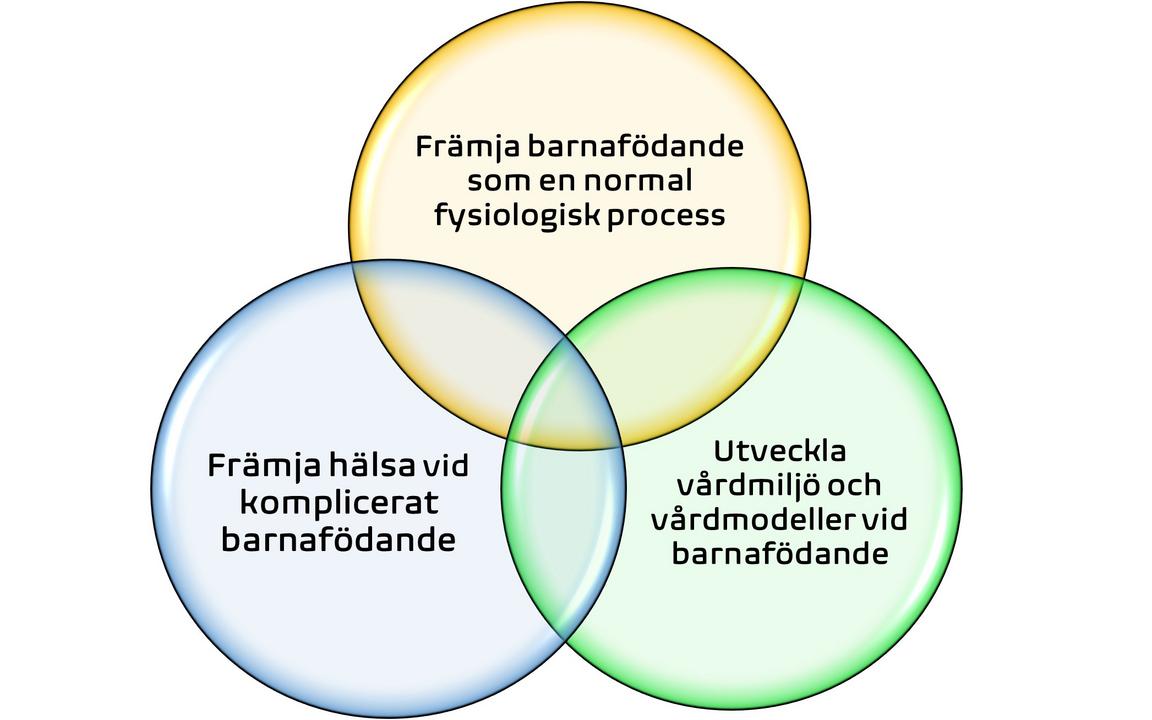

Utgångspunkten är att forskningen som bedrivs ska främja barnafödande som en normal fysiologisk process. Det finns flera olika forskningsinriktningar:

Barnafödande som en normal fysiologisk process

Hälsa vid komplicerade tillstånd relaterat till barnafödande och föräldraskap

Vårdmiljö och vårdmodeller vid barnafödande